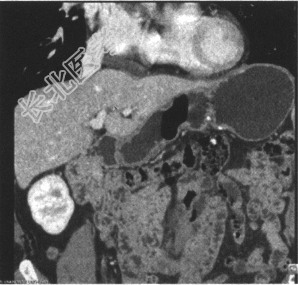

- 多项选择题5.[提示] 腹部CT示(见下图),肝左侧及胃窦下方囊性低密度影, 请结合临床除外复发可能。胃体大弯侧金属密度影,术后改变? 其下方类圆形软组织密度结节影,不除外复发或种植可能。

患者最有可能的诊断是( ) A、胃肠间质瘤